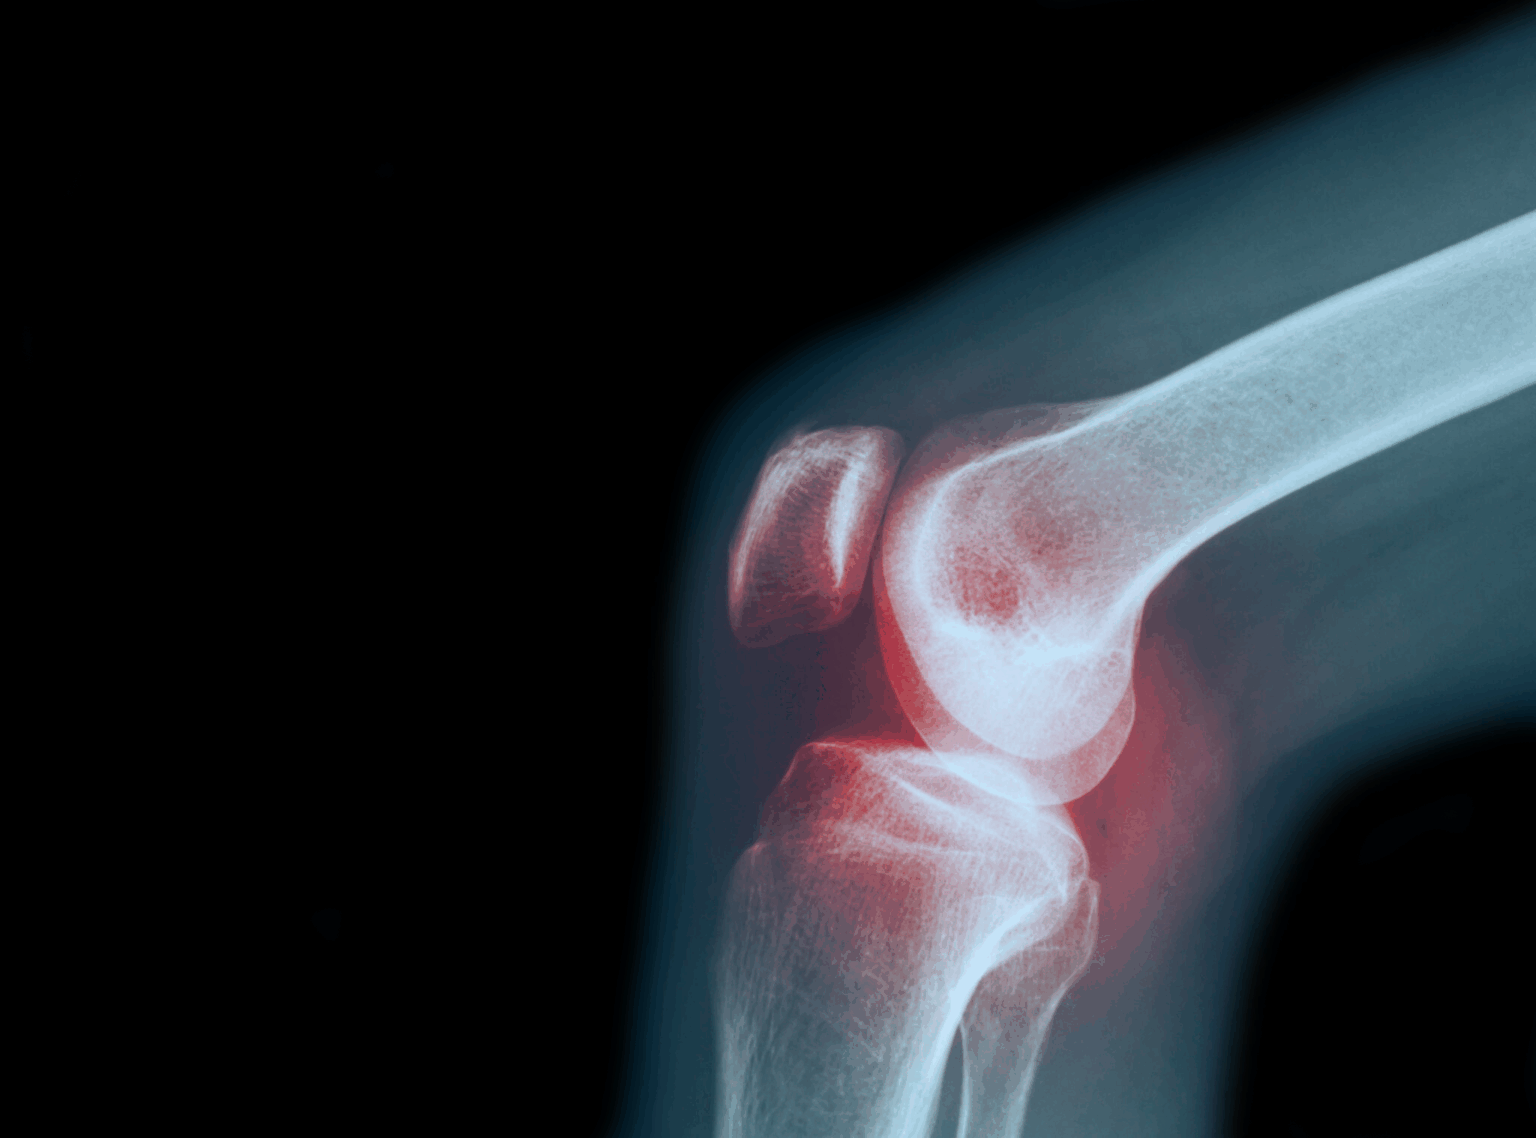

Although chronic osteoarthritis pain is often associated with loss of joint space, being "bone-on-bone" is not the direct cause of the pain, nor does it mean your joint is beyond repair.

At the ends of your bones is a hard shell of hyaline cartilage that protects the nerve endings within the bones. This hyaline cartilage is the same type 2 collagen found under the enamel of your teeth.

Over time, due to wear and tear, the articular cartilage thins, and tiny cavities form in the protective shell, a condition known as chondromalacia. These cavities leave the nerves in the bone less protected. As a result, normal activities like walking become painful.